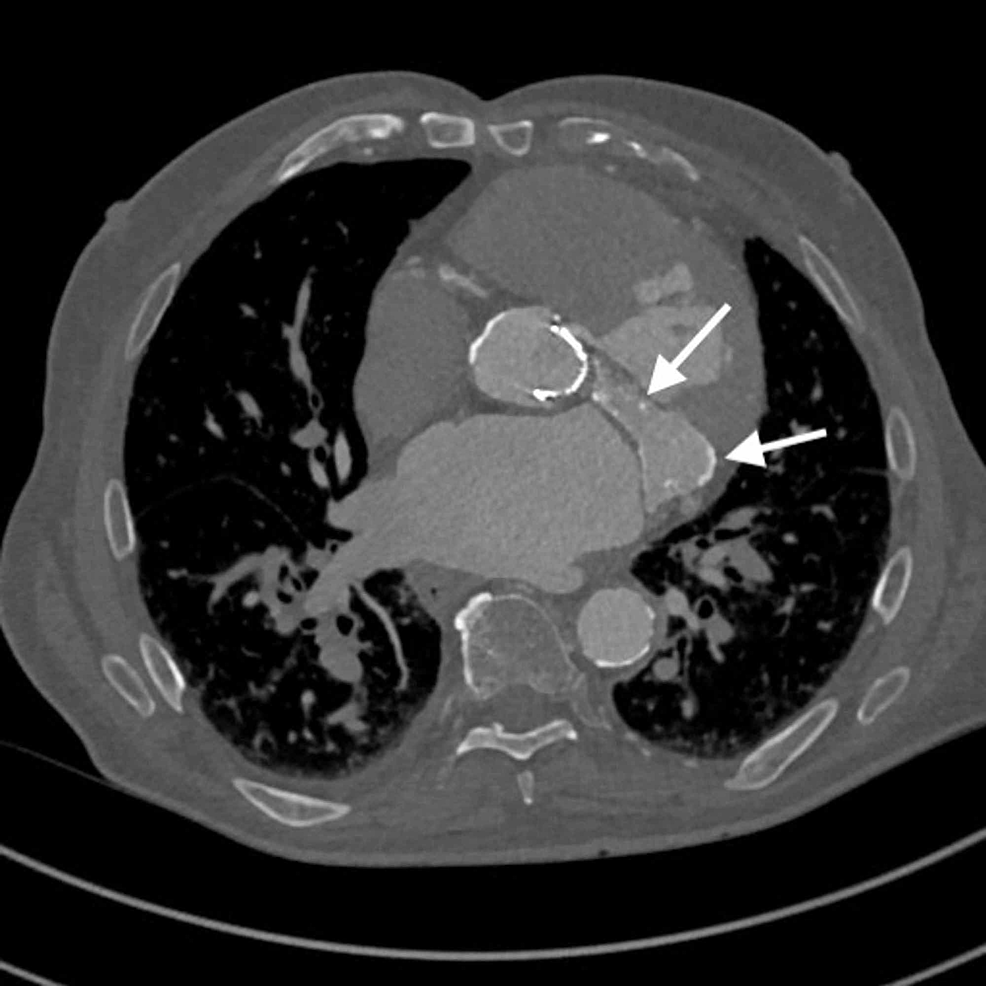

CT of the chest showing calcification of the mitral valve and no What Causes Calcium Deposits On Mitral Valve The mitral annulus is typically flexible. However, patients with disturbance in calcium and phosphate hemodynamics. Mitral valve dysfunction increased mortality, regardless. The presence of mitral annulus calcification was associated with higher mortality, after statistical adjustment. This can cause narrowing of the structures that support. Mitral valve prolapse is usually caused by problems with the tissues that join the mitral valve. What Causes Calcium Deposits On Mitral Valve.